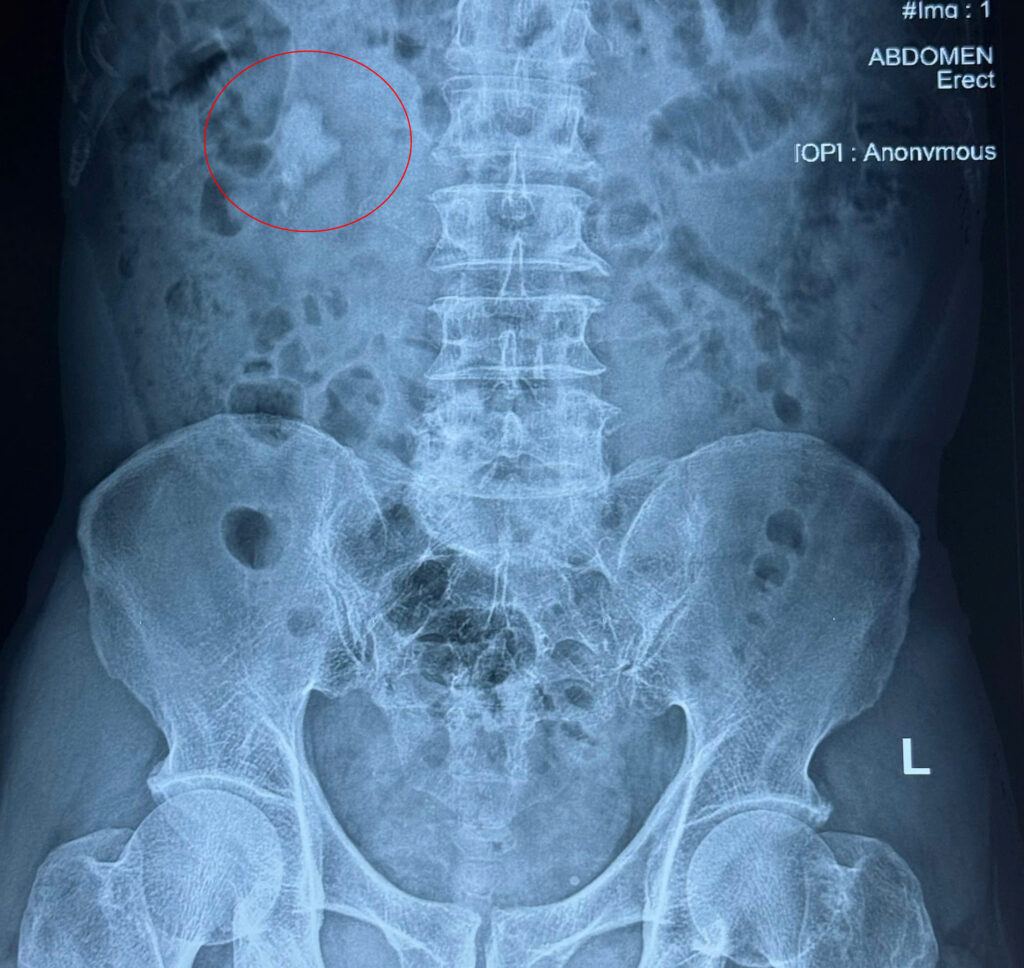

Được người quen giới thiệu, ông T. chọn Bệnh viện Quốc tế Thăng Long Lạc Việt. Tại đây, sau khi thực hiện các xét nghiệm chuyên sâu, bác sĩ phát hiện ông có sỏi san hô lớn ở thận phải (kích thước 25mm) – một dạng sỏi khó, cần phải can thiệp kỹ thuật cao.